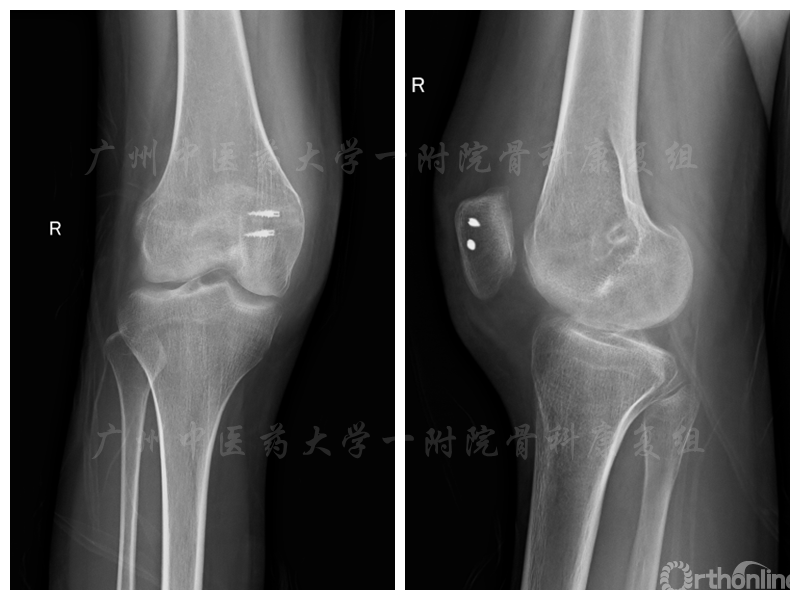

带着疑惑、忐忑、期待,雯雯来到了广州中医药大学第一附属医院运动损伤康复专科,找到了骨科康复团队。经过详细的体检评估,发现她的膝关节活动范围在5°—75°,右下肢由于长期制动,股四头肌、腓肠肌等肌肉萎缩明显,大腿周径较对侧少了近4CM。复查X片:右髌骨内侧金属影,符合术后改变,髌上囊肿胀;右膝稍外翻。

术后X光片